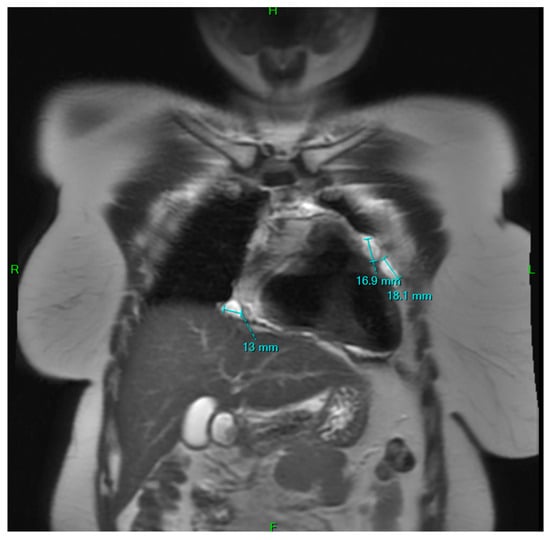

A Rare Case of Multilocular Mesothelial Inclusion Cysts of the Pericardium: Diagnosis, Treatment, Follow Up, with Comprehensive Review of the Literature

by Ali Shadmanian, Kosha Patel, Endre Alács, Henriette Gavallér, Szilva Agocs and Miklós Bitay

Background: Multilocular mesothelial inclusion cysts—also known as benign multicystic mesothelioma (BMM)—are rare, typically arising in the peritoneal cavity. Pericardial involvement is extremely uncommon and can pose diagnostic and therapeutic challenges due to their recurrent and infiltrative nature. Accurate diagnosis and surgical strategy are [...] Read more.

Background: Multilocular mesothelial inclusion cysts—also known as benign multicystic mesothelioma (BMM)—are rare, typically arising in the peritoneal cavity. Pericardial involvement is extremely uncommon and can pose diagnostic and therapeutic challenges due to their recurrent and infiltrative nature. Accurate diagnosis and surgical strategy are critical for management and recurrence prevention. Methods: We present the case of a 36-year-old woman with a prior history of malignant melanoma who developed recurrent multilocular cystic masses of the pericardium. Initial imaging with echocardiography, cardiac magnetic resonance (CMR), and computed tomography (CT) revealed multilocular pericardial cysts. Surgical resection was performed under cardiopulmonary bypass (CPB), but complete excision was limited due to epicardial infiltration. Histopathology confirmed a benign mesothelial origin. One year later, recurrence prompted a second surgical intervention with total pericardiectomy and Gore-Tex patch reconstruction. Results: Postoperative recovery was uneventful in both instances. Follow-up imaging at 6 and 12 months demonstrated no significant recurrence. Histological analysis confirmed benign cysts lined with mesothelial cells, positive for calretinin and WT-1. This represents one of the first documented living cases of pericardial BMM managed with staged surgery and total pericardiectomy. Conclusions: Pericardial BMM is a rare, benign, but potentially recurrent lesion. In cases of extensive or recurrent disease, total pericardiectomy may offer definitive treatment. Multimodal imaging, histopathological evaluation, and personalized surgical planning are essential for effective management. Full article

Figure 1